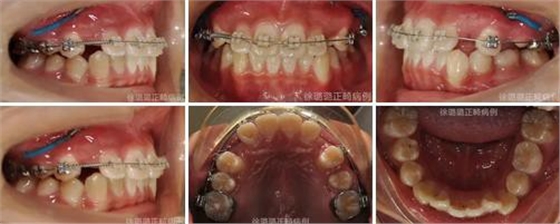

1.分別采用 .012 ~ .016" NiTi 圓絲和 .017 × .022"、.019 × .025" NiTi 方絲排齊整平上下牙列,口外弓推雙側(cè)磨牙遠(yuǎn)移。

2.0.45mm 不銹鋼圓絲糾正上頜中線不端正。

3..019 × .025" 方不銹鋼絲尖牙導(dǎo)萌,并通過種植體支抗釘牽引尖牙牙冠向遠(yuǎn)中移動,然后垂直向牽引尖牙向牙合方。

4.精細(xì)調(diào)整磨牙關(guān)系為中性關(guān)系,前牙覆牙合覆蓋關(guān)系至正常。

導(dǎo)萌術(shù)中口內(nèi)像

CT 片結(jié)果顯示,上頜雙側(cè)側(cè)切牙與尖牙位置較近,因此早期沒有粘結(jié)雙側(cè)側(cè)切牙托槽,以防止正畸加力對牙齒造成根尖吸收。